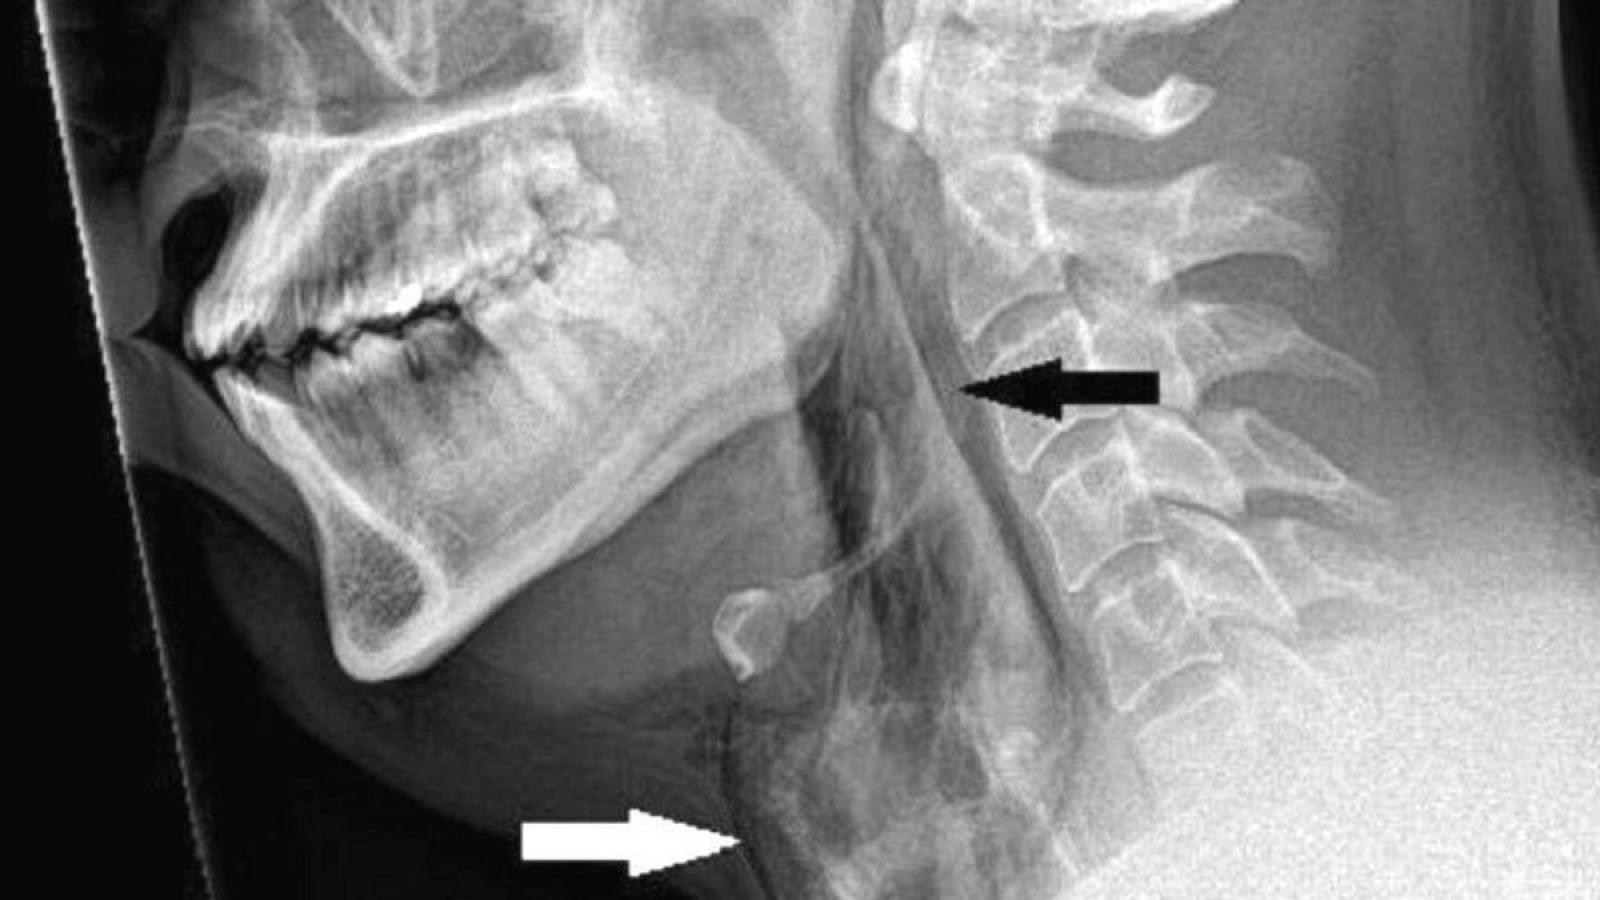

De acuerdo a la revista médica MJ Case Reports, el sujeto se apretó la nariz y cerró la boca para reprimir la acción, lo que le provocó un desgarro de 2 mm en la tráquea.

Según los médicos de la Universidad de Dundee, lo ocurrido se debió a la presión en las vías respiratorias, pues si se evita un estornudo con este mecanismo, el esfuerzo en la zona puede aumentar unas 20 veces.